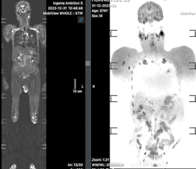

Trường hợp 3: Khảo sát WB-MRI đánh giá giai đoạn ung thư tại PKĐK 360 Lê Hoàn đối chiếu hình ảnh chụp PET-CT tại Khoa Y học hạt nhân - Bệnh viện K trung ương.

NB nam, 62 tuổi, đau ngực trái: U thuỳ trên cạnh rốn phổi trái, di căn hạch trung thất & hạch thượng đòn trái. (Biopsy hạch thượng đòn trái xác nhận hạch di căn)